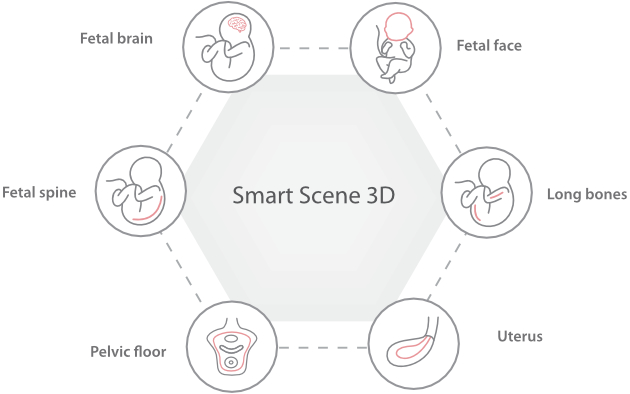

Nuewa I9, dirancang secara khusus untuk perawatan kesehatan wanita dan bayi baru lahir, menghadirkan pengalaman yang inovatif. Inovasi ini dikembangkan berdasarkan wawasan mendalam atas skenario klinis yang kompleks, memberikan jawaban yang akurat dan tepat waktu serta efisiensi dan pengalaman pengguna yang luar biasa.